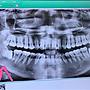

11F→: 我是都有割肉牙齒分2~3塊夾出來 比照片還深一點02/12 01:00

12F→: 傷口有縫線一個禮拜後去拆02/12 01:01

7F→: 我剛拔完下排水平智齒 前幾天有吃藥不會痛 拔完3-5天02/05 18:28

8F→: 最痛02/05 18:28

9F→: 我縫線一個禮拜後去拆的 傷口約兩週完全沒感覺02/05 18:29

10F→: 拔完第一天完全只喝水 第二天吃稀飯吃了五天給你參考02/05 18:30